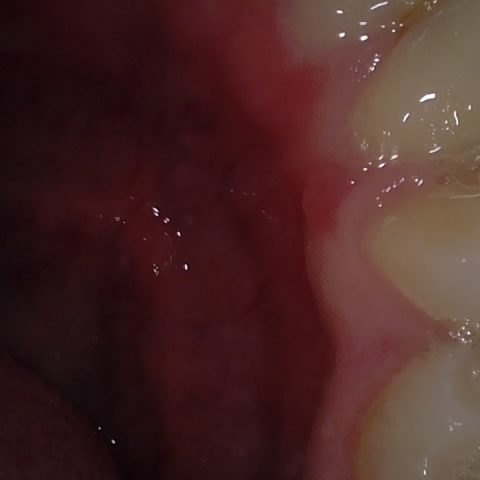

NHD20738

Annotated as "Good"